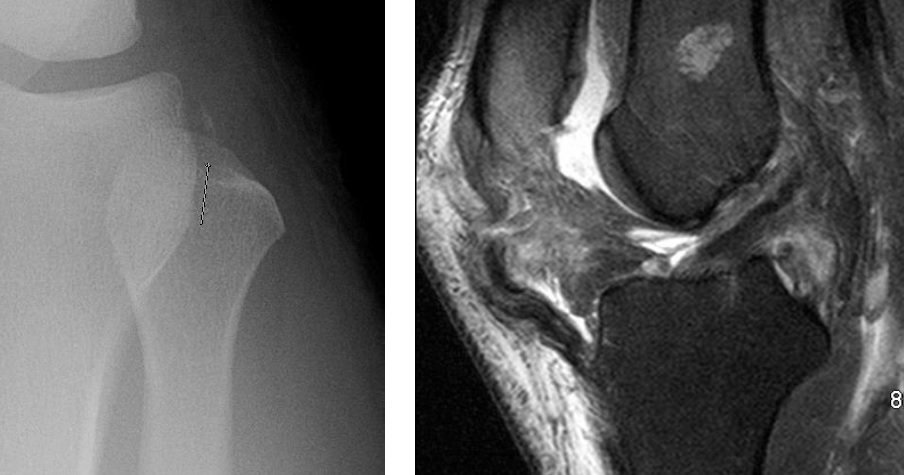

Identify

Segond fracture

Lipohemarthrosis

In which joint type is effusion generally most easily identified?

knee